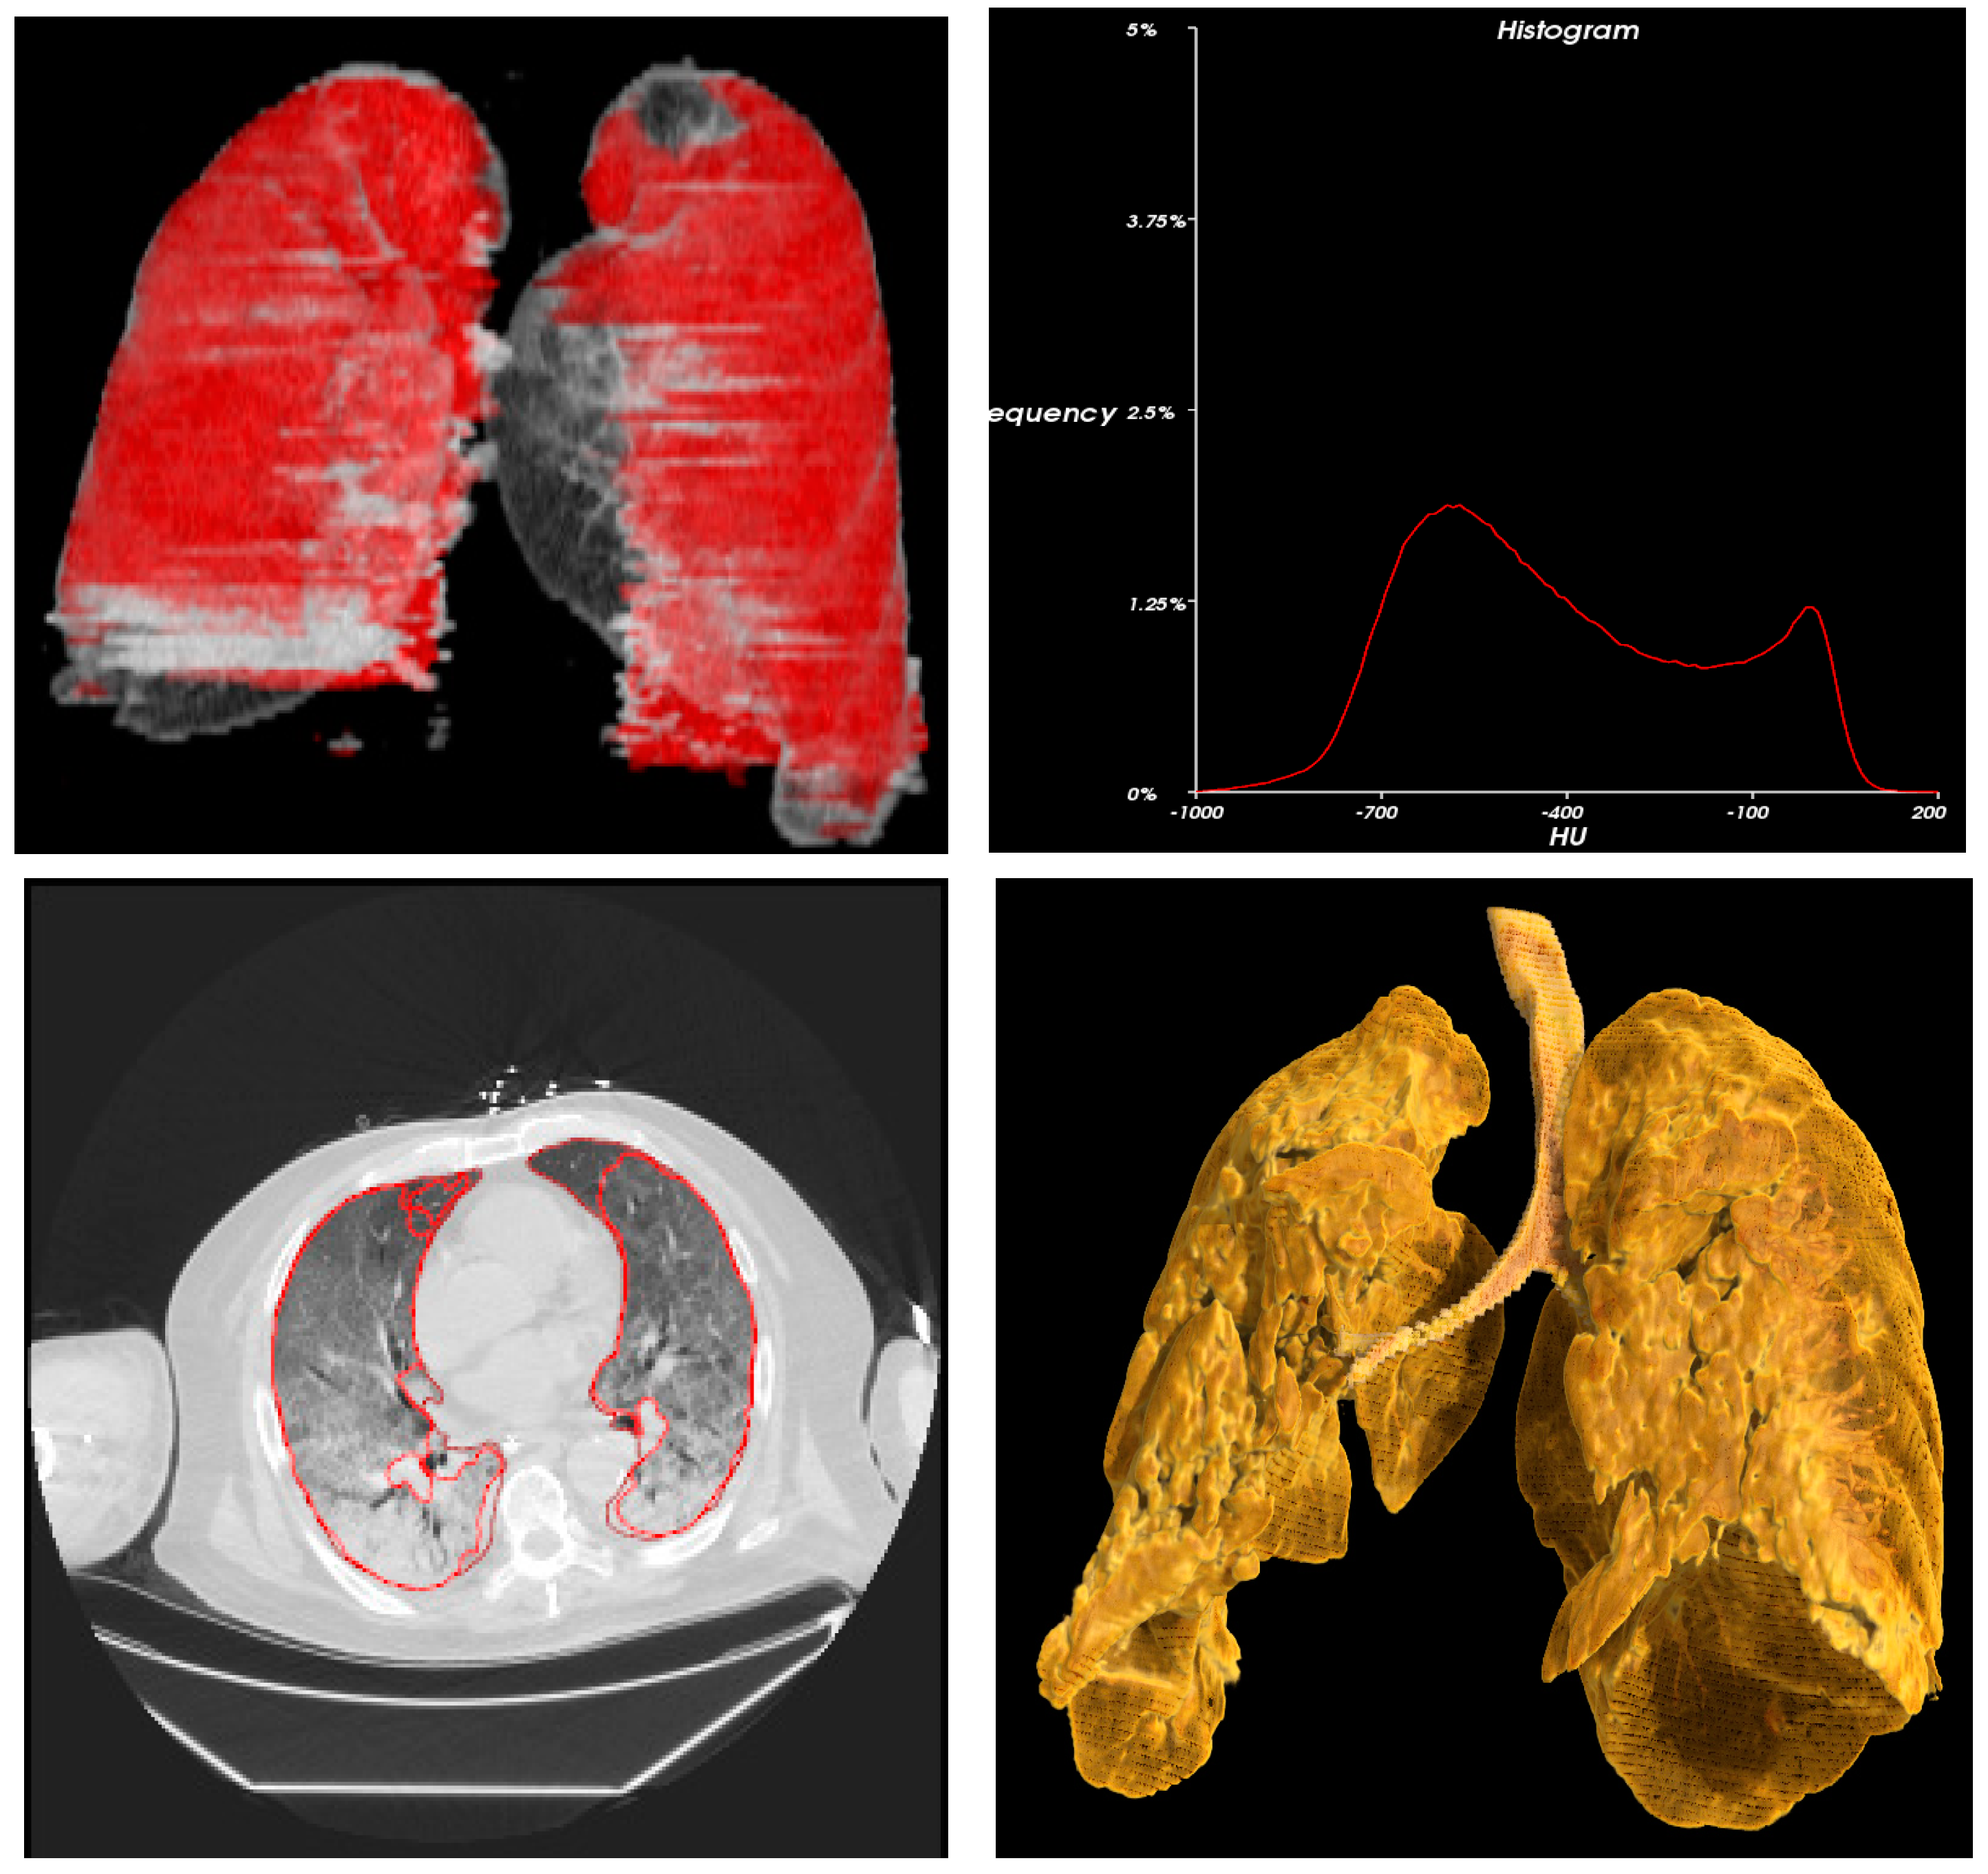

2.2. Study Procedure

2.3. Methods

2.4. Statistics and Data Analysis

3. Results